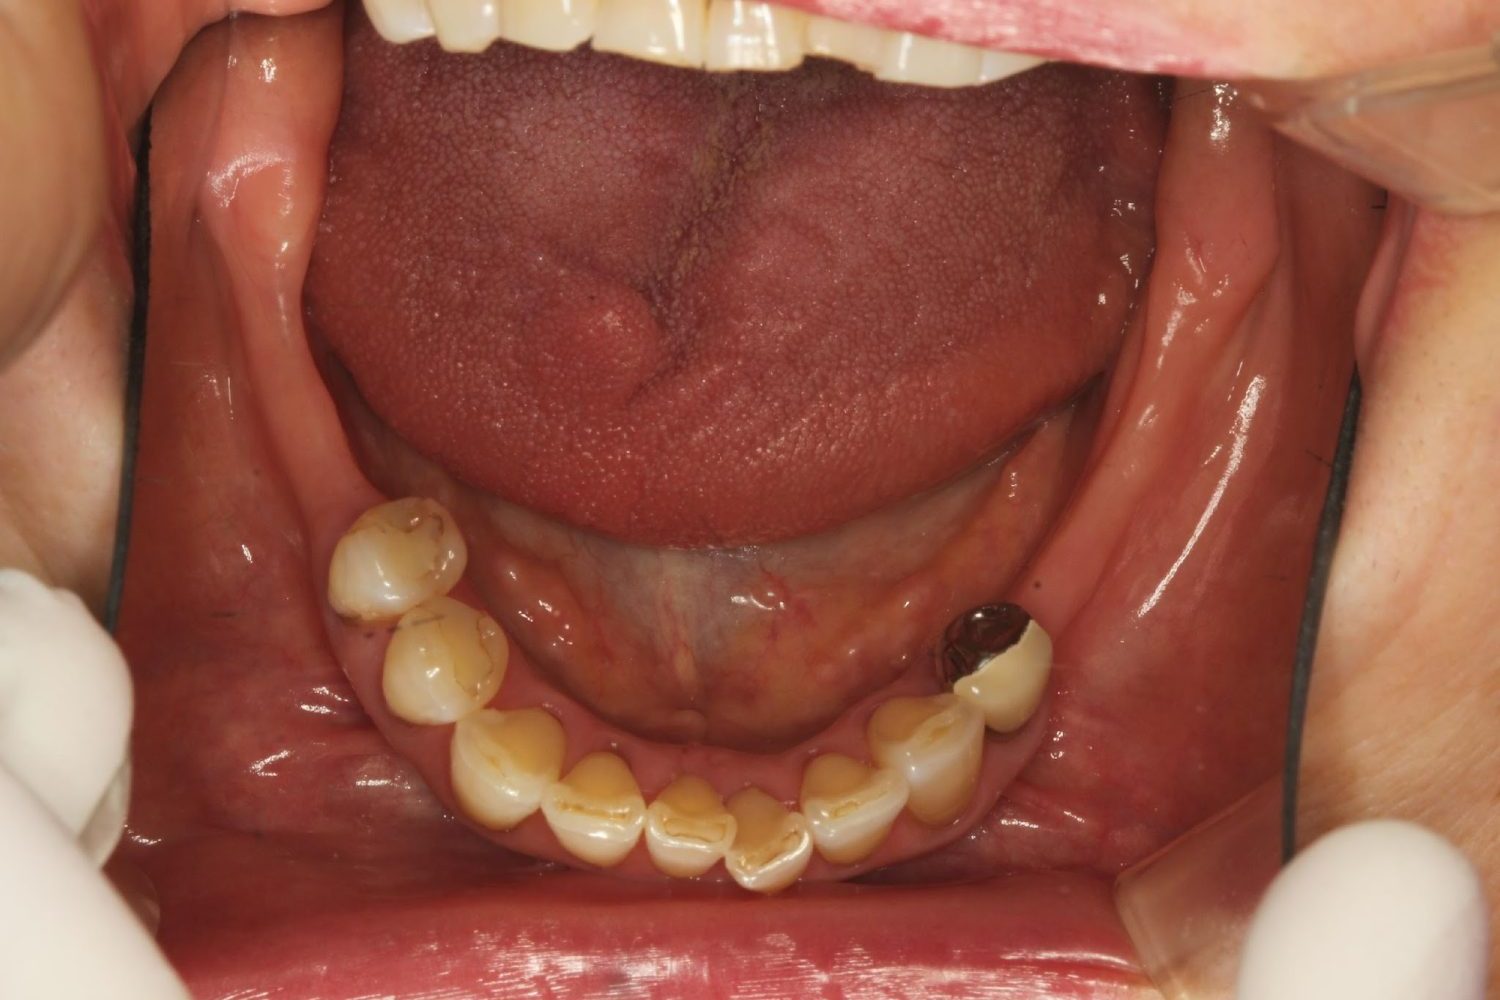

インプラント治療の症例紹介③

Before

After

主訴

むし歯の治療

治療内容

保存不可能な歯の抜歯

下顎にインプラント埋入し咬合再構成

治療費

2,688,400円(税込)

治療期間

14か月

治療回数

21回

想定されたリスク

※上部構造の形態が複雑になるため清掃が難しくなる。インプラント周囲炎の恐れがありました。

多数歯う蝕および多数歯欠損による咬合崩壊、保存不可能な歯の抜歯により上下無歯顎に。下顎に6本インプラント埋入する事で咬合再構成を行った。